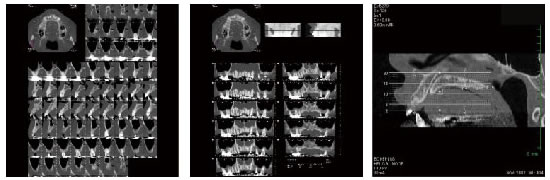

もちろん保険で撮影する2次元的なパノラマレントゲン写真でも大まかな診断は可能です。しかし、部位によってはパノラマレントゲンでは骨の厚みや神経の位置を正確にとらえることができないことがございます。経験や感覚で手術を行うことも可能ですが、より安全なインプラント治療を受けていただくためには、CTによる3次元的診断が必要であると考えております。

周辺組織の状態を三次元的に把握できます

顎の骨の中には神経や血管が通っています。特に神経は複雑に張り巡らされている部分もあり、平面的なパノラマレントゲンだけで正確にとらえるのは難しい場合がございます。

CT診断でより安全性の高い治療を行うことが出来るのはもちろん、CT撮影した画像を患者様にご覧いただきながらご説明することで、安心して治療を受けていただくことができるのではないかと考えております。